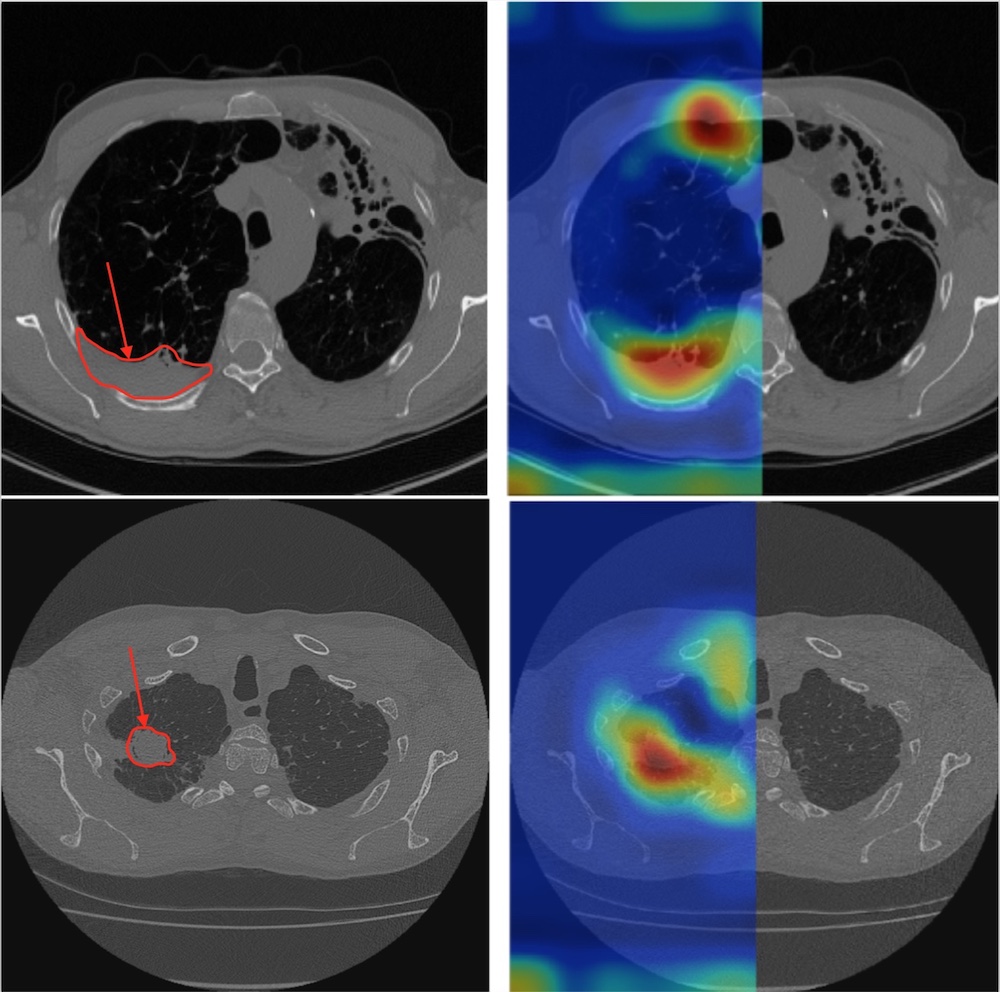

Test scores are best or close to best using axial views, for the three pathological signs. We illustrate in Fig. 3 two axial Grad-CAM activation maps, where We illustrate in Fig. 3 two axial Grad-CAM activation maps. In both figures, an original CT slice from a CPA patient is shown along with the gradient weighted activation map from the corresponding sub-region. We can observe that locations of maximum activation match very well with actual locations of pleura thickening and fungus balls.

Refer to caption

Fig. 3: Localization of pathological signs using axial projections on CPA subjects with pleura thickening (top) and a fungus ball (bottom). The original axial slice (left) and the overlaid grad-CAMs (right) are shown.